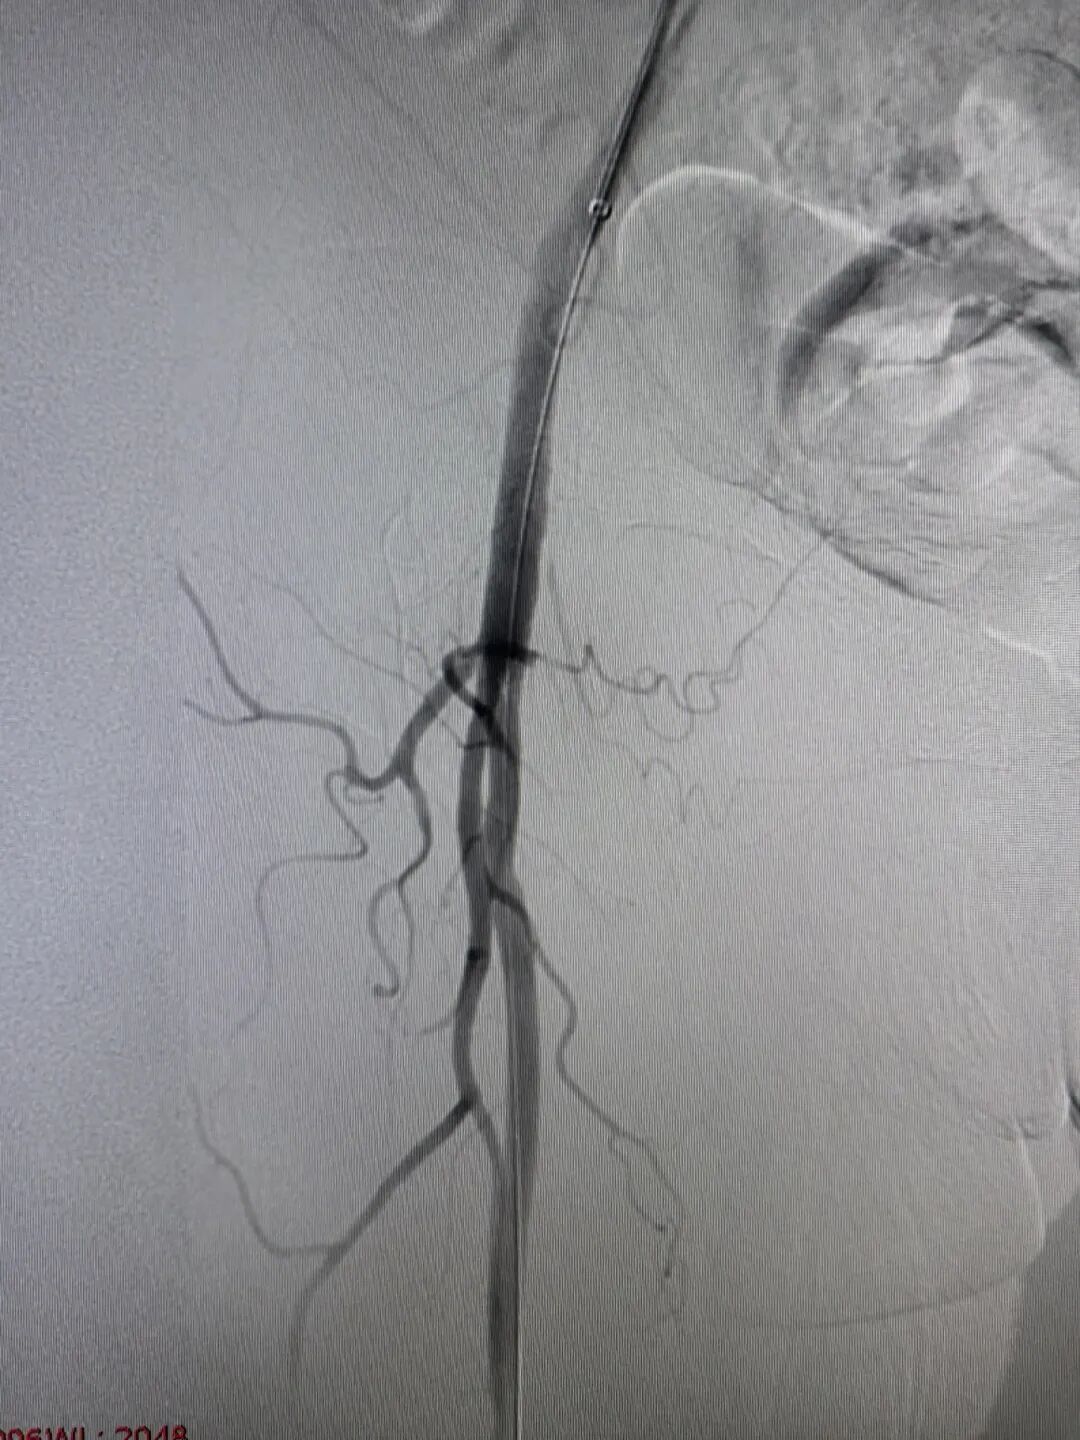

a0a1e537118f198eda9331c83e1efd2a.jpeg 5a665816715e62930adbc5c389d5b167.jpeg

(介入术后闭塞的血管完全再通)

两个小时后,手术顺利完成。孙奶奶右下肢的皮温、皮色即刻改善,足背动脉搏动恢复,疼痛麻木消失。从入院到血运重建,全程高效顺畅,没有浪费一分一秒。